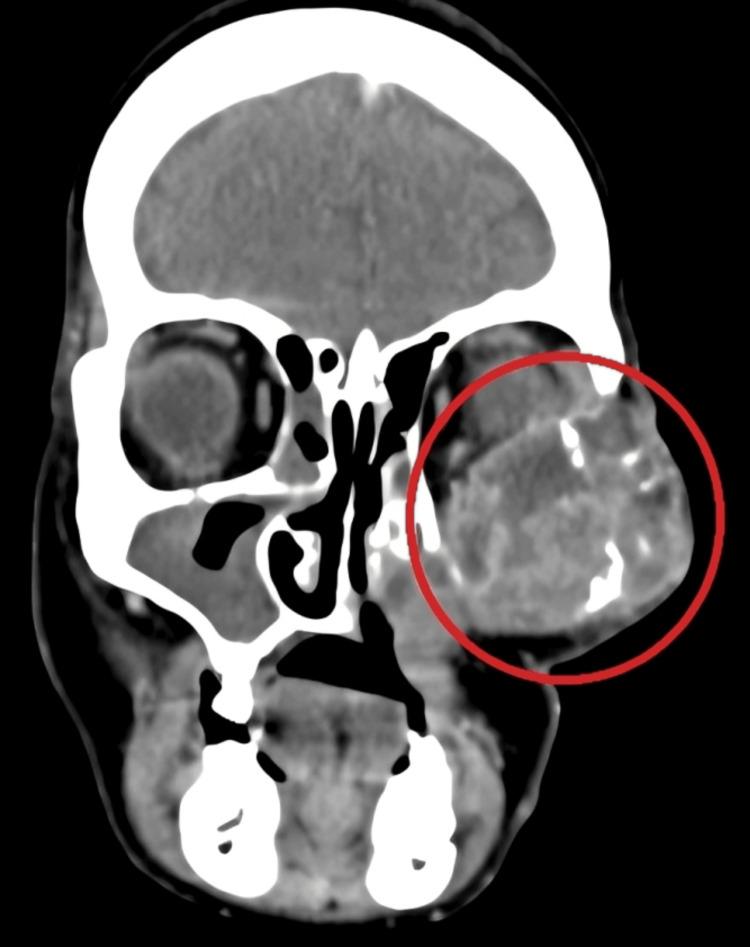

Epithelial-myoepithelial carcinoma (EMC) is a rare tumor, characterized by two different cell populations and both demonstrate a malignant nature microscopically. It constitutes less than 2% of all salivary gland malignancies. The World Health Organization (WHO) has classified this disease as a separate pathological category. The diagnosis of this tumor is arrived by biopsy. It shows slow growth and is small in size; it appears in ulcerative form of mucosa in some cases. Gland cells consist of two layers of outer myoepithelium cells and inner epithelial cells. Vimentin staining is positive. It shows calponin, muscle-specific actin, S100, smooth muscle actin, p63, and smooth muscle myosin heavy chain I. Examining different sets of data reveals that tumors exhibiting a solid growth pattern, nuclear atypia, DNA aneuploidy, and increased proliferative activity typically display a more aggressive nature, accompanied by a heightened likelihood of local recurrences and metastases. The clinical and radiological observations frequently resemble those of a benign tumor. Due to the uncommon nature of EMC, there is currently no established standard treatment protocol. It is considered a low-grade tumor where good resection holds better results. Individuals displaying histopathological indicators of aggressive disease should be evaluated for potential adjuvant radiotherapy. We present a case of a patient who had recurrence twice in a period of seven years despite surgical management, chemotherapy, and radiotherapy.

上皮-肌上皮癌(EMC)是一种罕见肿瘤,其特征为两种不同的细胞群,且在显微镜下均显示恶性特征。它占所有涎腺恶性肿瘤的比例不到2%。世界卫生组织(WHO)已将这种疾病归类为一个单独的病理类别。该肿瘤通过活检进行诊断。它生长缓慢且体积较小;在某些情况下,它以黏膜溃疡性形式出现。腺细胞由外层两层肌上皮细胞和内层上皮细胞组成。波形蛋白染色呈阳性。它显示钙调蛋白、肌肉特异性肌动蛋白、S100、平滑肌肌动蛋白、p63和平滑肌肌球蛋白重链I。对不同数据集的研究表明,呈现实体生长模式、核异型性、DNA非整倍体和增殖活性增加的肿瘤通常具有更具侵袭性的特征,同时局部复发和转移的可能性更高。临床和影像学表现常常类似于良性肿瘤。由于EMC较为罕见,目前尚无既定的标准治疗方案。它被认为是一种低级别肿瘤,手术切除效果较好。对于表现出侵袭性疾病组织病理学指标的个体,应评估其是否适合进行辅助放疗。我们报告一例患者,尽管接受了手术治疗、化疗和放疗,但在七年时间内复发了两次。